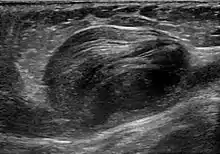

A false aneurysm, or pseudoaneurysm, is a collection of blood leaking completely out of an artery or vein but confined next to the vessel by the surrounding tissue. This blood-filled cavity will eventually either thrombose (clot) enough to seal the leak or rupture out of the surrounding tissue.[3]: 357

Pseudoaneurysms can be caused by trauma that punctures the artery, such as knife and bullet wounds,[4] as a result of percutaneous surgical procedures such as coronary angiography or arterial grafting,[5] or use of an artery for injection.[6]